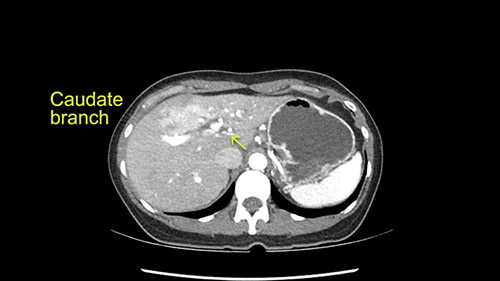

My plan would be to leave the caudate lobe intact. You usually have to divide the caudate branches. I can see one of the caudate branches here coming off the left portal vein. You usually have to take that to get adequate length although you might be able to divide the portal vein past that left caudate branch.